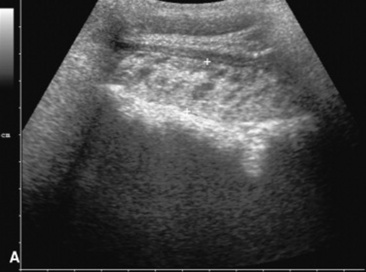

In the last 5 years ultrasound has come to the forefront of evaluation of the equine alimentary tract, primarily centering on the abdomen. Ultrasound has been used in foals to determine the growth rate and normal appearance of thoracic and abdominal organs18 and in adult horses to evaluate the gastrointestinal tract for causes of pain including torsion, small intestinal obstruction, colon impaction, large colon displacement, intussusception, strangulating lesions, and enteritis and colitis.10,19-23 This modality is even more useful because it provides real-time information to help assess contractility of the intestine. Although this has been explored using both standard two-dimension imaging, also called B-mode or brightness-mode imaging, and spectral Doppler imaging,24 the presence of gas within the bowel and the fact that the bowel is usually perpendicular to the image plane makes quantitative evaluation of intestinal contractility difficult at best. When compared with radiography to identify intestinal sand accumulations, ultrasound was found to be 87.5% sensitive and specific using radiography as the gold standard.10 The main limitations are the artifacts secondary to gas within the colon and the fact that gas and mineral are both echogenic on ultrasound, whereas they have opposite opacities on radiographs.

Ultrasound evaluation of horses with abdominal pain (colic) provides a rapid method to identify abnormalities within the gastrointestinal tract. Distention of the small intestine to a diameter greater than 5 cm has been strongly associated with strangulating or obstructing lesions19 (Fig. 32-11). In foals with intussusception, the small intestine appears enlarged and there is generally distended small intestine orad to the lesion; however, at the site of the intussusception there is a normal-appearing small intestinal wall (intussuscipiens) surrounded by a larger structure that appears to surround the inner small intestinal wall (called the intussusceptum)19 (Fig. 32-12). Large colon torsion occurs when the large colon rotates 360 degrees or more around the root of the mesentery to cause occlusion of venous drainage while maintaining arterial flow. This causes the wall to become thick and edematous. If ultrasound is performed in the cranioventral abdomen, just caudal to the xiphoid process, then a colon wall size greater than 9 mm is 100% specific for a large colon torsion21 (Fig. 32-13). A large colon displacement would have minimal to no vascular compromise, so it would be an ultrasound diagnosis based on exclusion. Chronic displacements did have a mild amount of edema in the colon wall, causing the size to be approximately 7 mm thick but never greater than 9 mm in the one study described.21 The colon and small intestinal wall will also become thick with inflammation. Small intestinal wall thickness greater than 4 mm is indicative of inflammation.19 The right dorsal colon can be imaged in the right tenth to twelfth intercostal space around the region of the costochondral junction, and a focal wall thickness of 9 to 12 mm has been identified with right dorsal colitis.23

Fig. 32-11 Transabdominal ultrasonographic image of a 6-year-old thoroughbred gelding with acute onset of colic. The small intestine is 7 cm in diameter and was noted to have minimal to no contractility. This is consistent for mechanical ileus. A strangulating lipoma was identified at surgery.